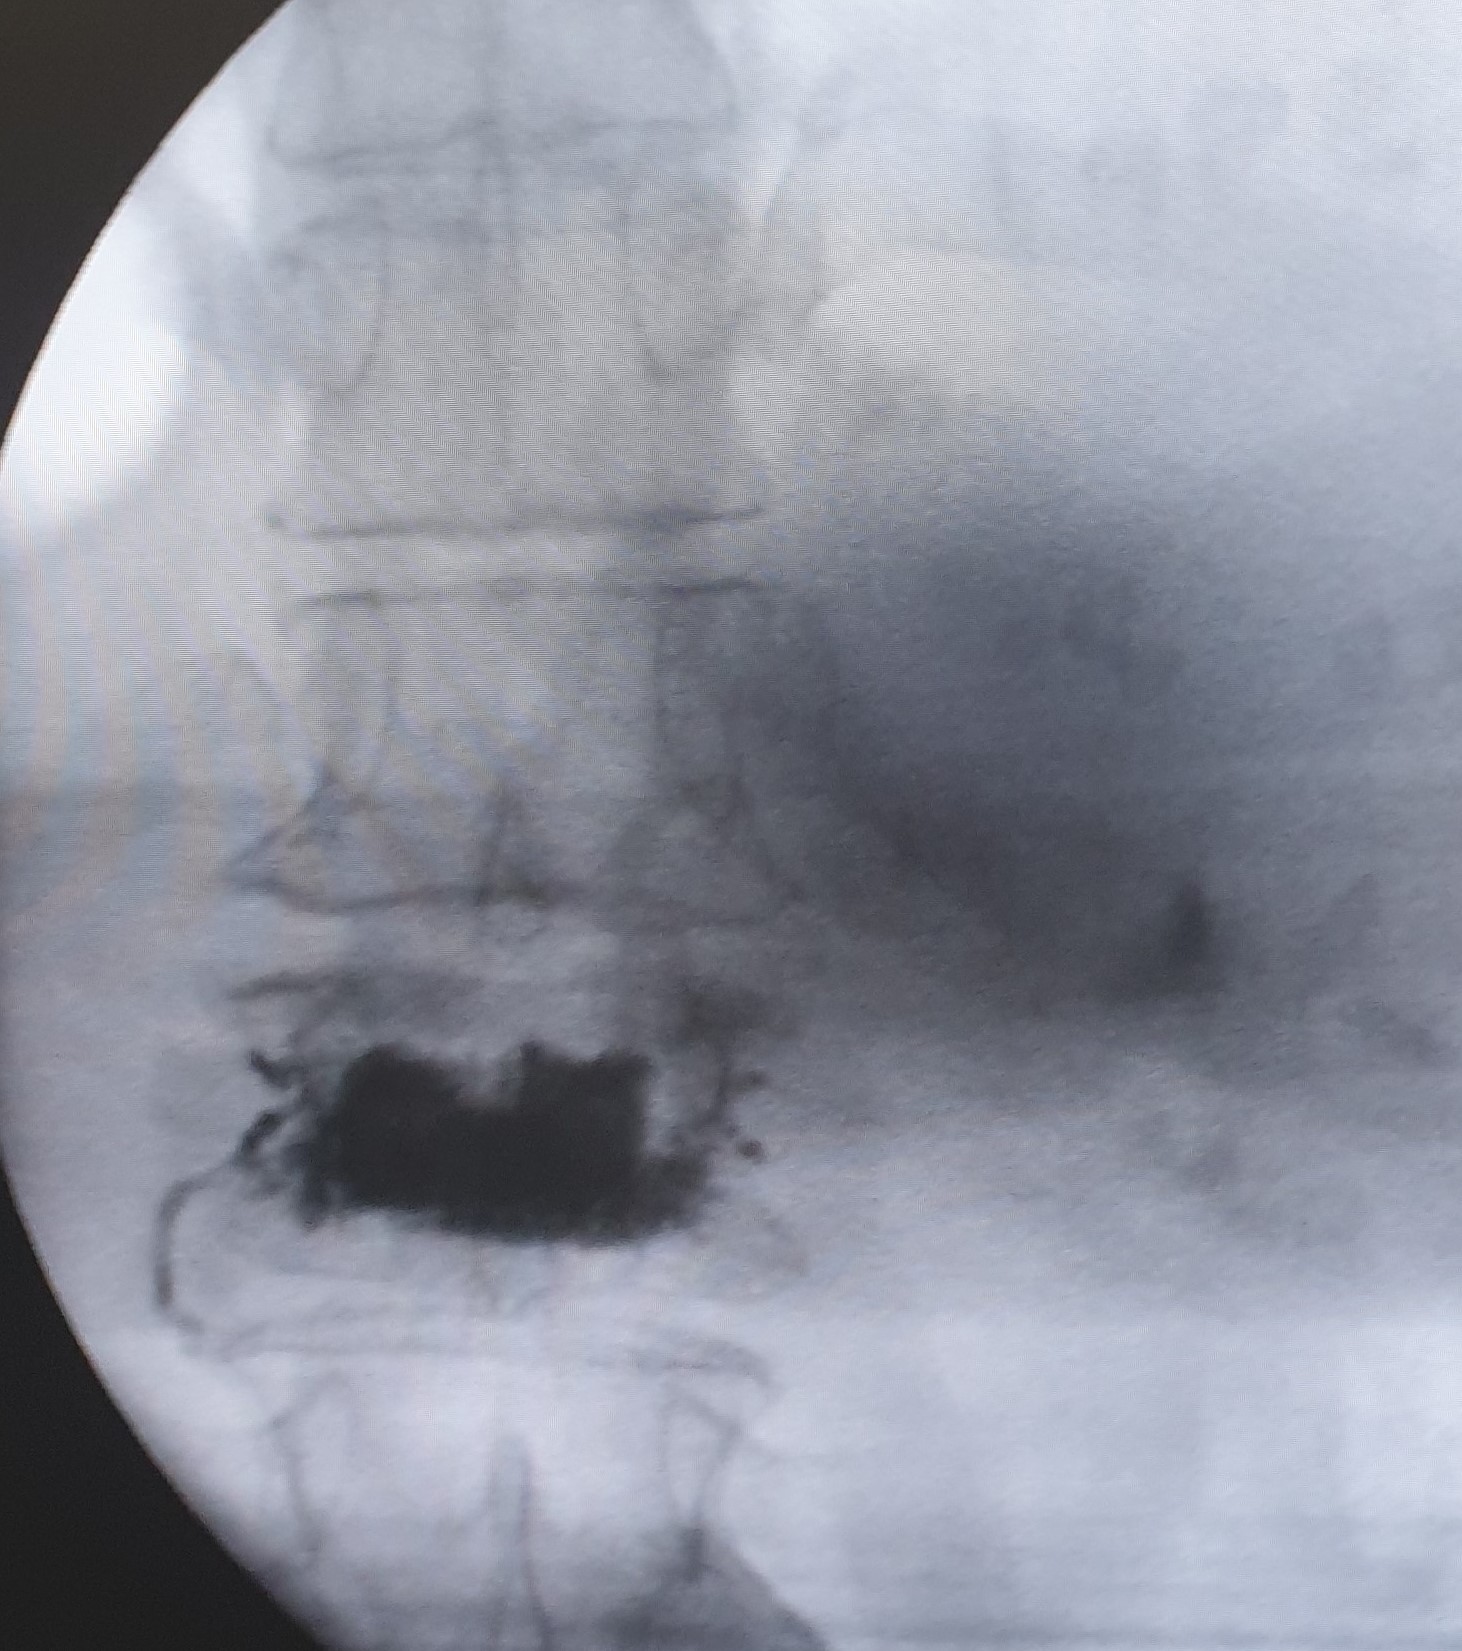

Η κυφοπλαστική και η σπονδυλοπλαστική αποτελούν ελάχιστα επεμβατικές τεχνικές αντιμετώπισης του πόνου που προκαλείται από συμπιεστικά καταγμάτα των σπονδύλων, επί εδάφους οστεοπόρωσης ή μεταστατικής νόσου. H προσπέλαση και στις δύο περιπτώσεις γίνεται διαδερμικά και κάτω από συνεχή ακτινοσκοπική καθοδήγηση.

Η κυφοπλαστική αποκαθιστά το ύψος του σπονδύλου, με χρήση ειδικού μπαλονιού και εισαγωγή τσιμέντου, ενώ η σπονδυλοπλαστική αφορά σε απλή εισαγωγή τσιμέντου στον καταγματικό σπόνδυλο. Και οι δύο τεχνικές γίνονται μέσω ειδικών βελόνων-trocar που εισάγονται διαδερμικά υπό ακτινοσκοπικό έλεγχο, στους αυχένες των σπονδύλων και προωθούνται στο σπονδυλικό σώμα, όπου γίνεται η έγχυση του τσιμέντου ταχείας πήξης. Το τσιμέντο σταθεροποιεί τον σπόνδυλο και αποτρέπει την ανάπτυξη κύφωσης στα πάσχοντα σημεία.

Η κυφοπλαστική επιλέγεται για πρόσφατα κατάγματα (έως 6 μηνών). Και οι δύο τεχνικές μπορούν να εφαρμοσθούν σε πολλαπλά επίπεδα της σπονδυλικής στήλης.